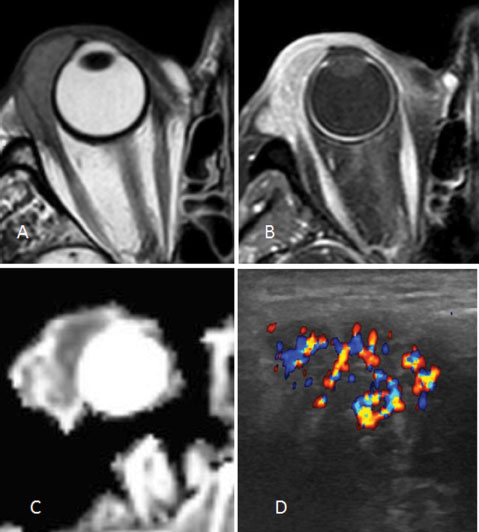

Figure 2

Lachrymal gland lymphoma T2-weighted (A), Post-contrast fat saturated T1-weighted (B), ADC (C), CDFI (D).